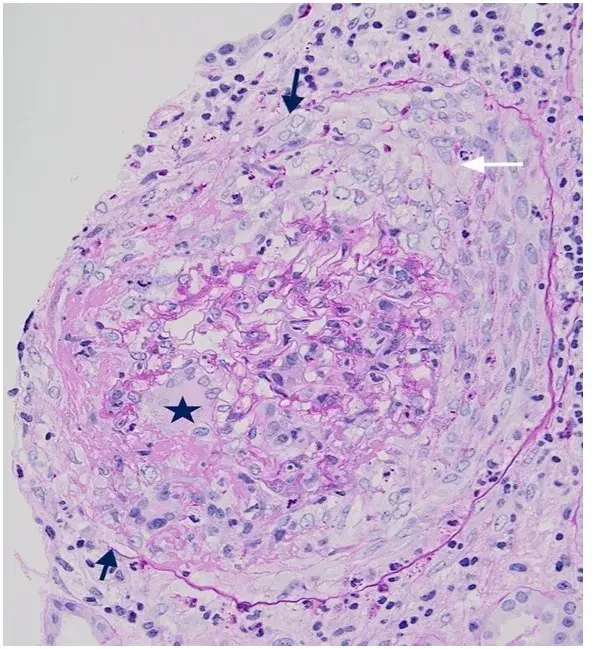

É possível identificar um glomérulo com quebra ruptura da MBG, com crescente celular no espaço de Bowman (seta branca), célula gigante multinucleada (estrela) e ruptura da cápsula de Bowman (seta preta) (PAS; 400×). PAS, ácido periódico-Schiff.

A biópsia renal revelou GN crescêntica necrotizante difusa sem hipercelularidade endocapilar. Alguns raros glomérulos continham células gigantes multinucleadas.

A avaliação da microscopia de luz pode ajudar na diferenciação de casos de **GN por anti-MBG** de casos **GN-ANCA**, já que na GN anti-MBG não observamos hipercelularidade endocapilar e pode ser identificado a presença de células gigantes multinucleadas, estas células gigantes multinucleadas resultam a natureza explosiva e a rápida destruição dos glomérulos observadas em anti-MBG

Desta forma, a presença de lesões crescentes temporalmente semelhantes e células gigantes multinucleadas na microscopia de luz (MO) pode ajudar no diagnóstico precoce.